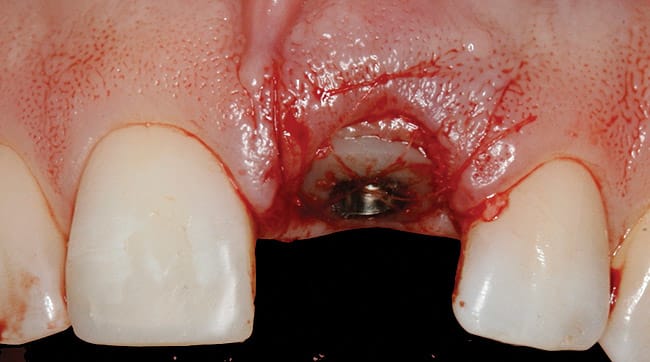

This case involved an ankylosed left central incisor. The patient’s chief complaint was that the incisor was dark and discolored (Figure 9 and Figure 10). Several possibilities were considered, including retaining the tooth or replacing it with an implant. The issue with retaining the incisor concerned the large pulpal canal and the need to aggressively prepare the tooth for a crown in order to mask the dark unesthetic dentin. Another concern was the long-term probability of external root resorption since it was ankylosed. The decision was made to extract and place an implant. The patient had good bone and good soft-tissue positions. The treatment plan was to extract and place the implant with an immediate protocol. The use of an immediate provisional was also considered, but the patient’s deep overbite and his desire to not have to be protective of the implant made the case for doing a bonded provisional. The incision design was done to allow for a facial flap but preserve the papilla. The extraction of the ankylosed incisor required magnification to dissect the tooth from the bone. The implant was placed and the site was grafted with hard and soft tissue. Figure 11 shows the implant, custom healing abutment, CTG, and closure with 7.0 vicryl sutures.

The final soft-tissue form was transferred with the impression by fabricating a custom impression coping, which was made with flowable composite and mimicked the cervical portion of the provisional restoration (Figure 12). The final restoration achieved the patient’s goal of matching the color and esthetic contours with the adjacent teeth. The gingival esthetics were ideal, making the implant undetectable from the natural dentition (Figure 13).